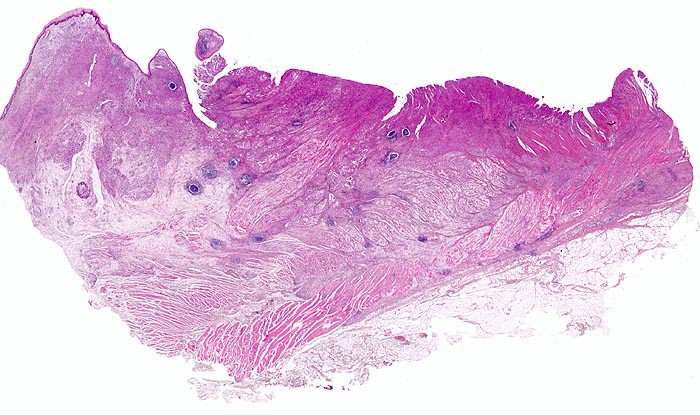

Adenokarzinom des Magens

Oesophagogastrischer Uebergang

Links im Bild der Ösophagus mit intaktem plattenepithelialem $o{ay37517Schleimhautüberzug} Schleimhautüberzug. Rechts der proximale Magen. Das unscharf begrenzte Karzinom breitet sich diffus in der gesamten Magenwand aus. Rechts im Bild sieht man die durch den Tumor aufgesplitterte Muscularis propria. Ausserdem breitet sich der Tumor submukös im Ösophagus aus.

Diffuse Verdickung und Versteifung der Magenwand im Sinne einer Linitis plastica bei intakter Schleimhautoberfläche. Aufhebung des Faltenreliefs.

Die Magenkarzinome können nach Lauren in einen intestinalen und einen diffusen Typ eingeteilt werden. Karzinome vom intestinalen Typ bestehen aus Karzinomdrüsen, welche einen umschriebenen expansiv wachsenden Tumor bilden. Der diffuse Typ besteht aus Tumorzellen, welche keine Drüsen bilden sondern die Magenwand einzeln oder in kleinen Verbänden diffus infiltrieren. Meist handelt es sich dabei um den histologischen Subtyp von Siegelringkarzinomen. Daneben gibt es auch eine Mischform mit Anteilen vom diffusen und vom intestinalen Typ.

Histologie

Scan